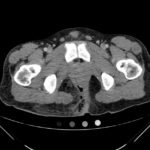

The computed tomography (CT) of the abdomen and pelvis revealed significant subcutaneous gas tracking along the perineum and right gluteal region (orange outline) into the scrotum with associated scrotal edema (yellow arrow) and subcutaneous inflammatory fat stranding of 0.92 cm (red arrow) consistent with Fournier’s gangrene. There is early fluid loculation along the right medial gluteal cleft of 5.85 cm (green arrow) without a sizeable drainable abscess seen.